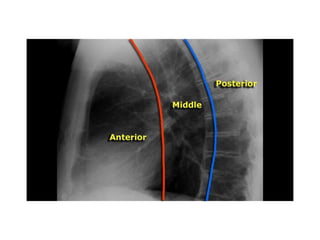

hili

• Once you know how the normal hilar structures look like on

a lateral view, it is easier to detect abnormalities.